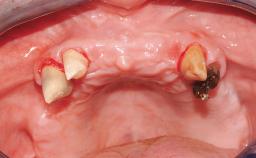

Conventional Loading of Eight Implants in the Maxilla and Final Restoration with a Full-Arch Gold-Ceramic FDP

A 35-year-old Caucasian female presenting with advanced periodontal disease involving both the maxillary and the mandibular dentition was referred for evaluation. The patient, a non-smoker in good general health, requested treatment for recurrent periodontal abscesses, tooth mobility, and discomfort during chewing, as well as restoration of her missing teeth with a fixed prosthesis to improve mastication and esthetics. All residual maxillary teeth exhibited plaque deposits, deep pockets, bleeding on probing, and class III mobility and were evaluated as hopeless. All residual mandibular teeth except tooth 37 could be maintained after periodontal therapy.

Soft Tissue Anatomy Intact Defective

Bone Volume Horizontally and vertically sufficient Horizontally deficient Deficient vertically or deficient vertically AND horizontally

Bone Volume Deficient vertically or deficient vertically AND horizontally